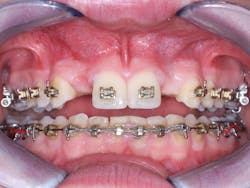

1. From a facial orientation, place the implant osteotomies in the center of the edentulous space from a mesial and distal orientation, using periapical radiographs to verify the parallelism and appropriate distance from the adjacent teeth (figure 3).

2. In the facial-lingual orientation, locate the osteotomies in the center of the ridge and parallel with the adjacent teeth. Use finger contact on the facial and lingual of the ridge while making the drill cuts. If you feel extra vibration on one or the other side of the ridge, reorient the drill appropriately (figures 4-7).

Figure 3: It is easy to center the implant osteotomy between the two adjacent teeth using your own clinical judgment and periapical radiographs.

Figures 4-7: This series of images shows a clinical situation, the cone beam images, and the freehand implant placement.